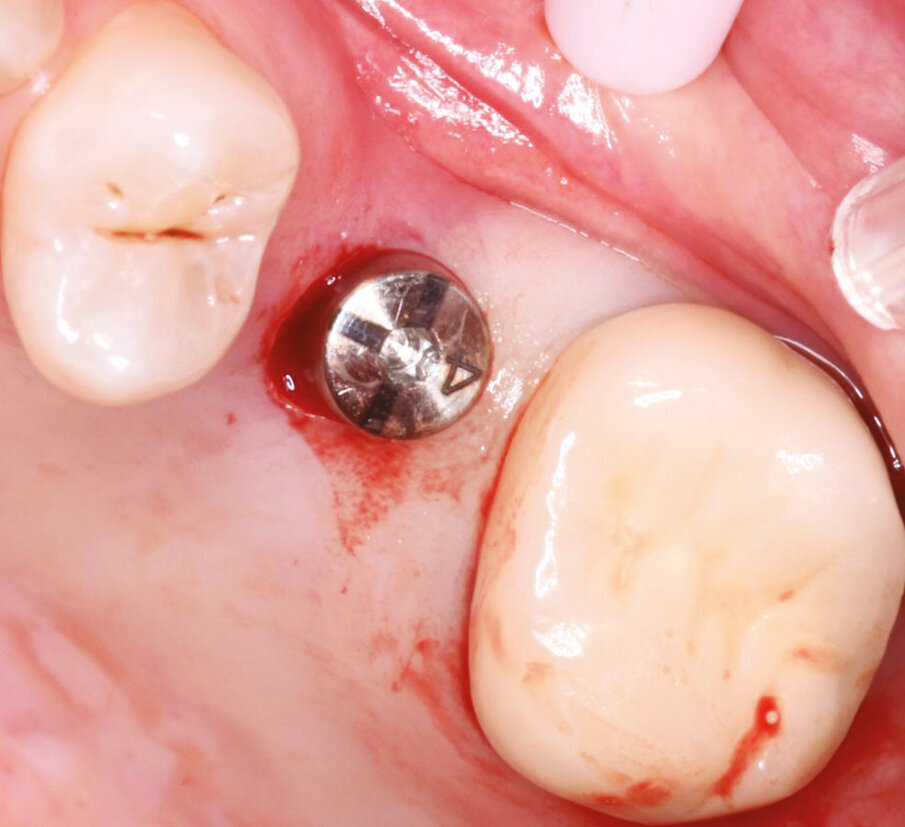

Fig.10: Axiom placement to 0,5 mm below crest of bone.

Fig.11: Second implant site prepared and tissue removed for flapless approach.

Fig.12: Heal check and Healing cap removal – note the proper tissue emergence profile and excellent health.

Fig.13: Heal check and Healing cap removal – note the proper tissue emergence profile and excellent health.